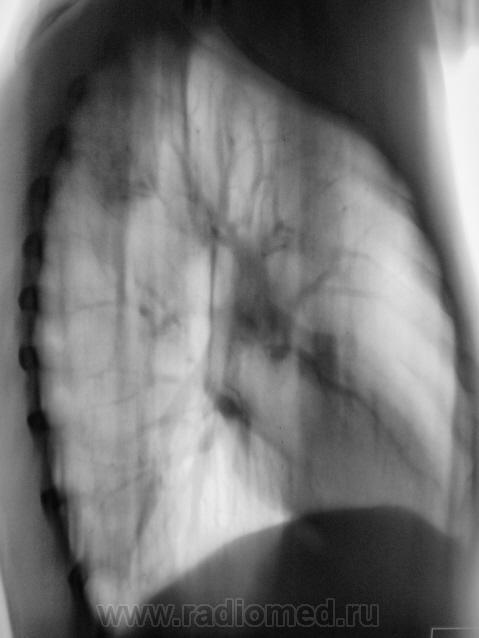

Томограммы в боковой проекции.

3 срез.

Думаю, больше данных за туберкулому. Интенсивность, структура, изменения фиброзно-очагового характера в окружающей ткани, в т.ч. подтягивание плевры. 90% за ТБС.

Доброго дня! И нет ничего удивительного в положительных посевах, в S2 справа нормальная такая туберкулема с участком просветления за счет распада и дренирующим бронхом, даже без ТГ видно, ежели б мокроту тщательнее смотрели (много значит опыт лаборанта) - скопически бы поймали КУМ,  а так посев только 2 мес. растет.

Туберкулома в S4.